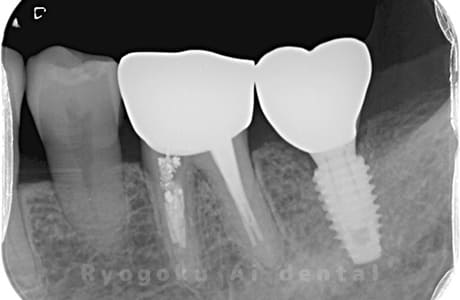

Case07

-

- 原因

- 右下6番歯根破折

- 治療内容

- インプラント治療

- 治療費用

- 約600,000円

右下の腫れが治らないとの事でご来院された患者様です。歯が割れていたため、抜歯を行い、骨に代わるお薬を入れ、インプラントを埋入致しました。経過良好で大変満足していただけました。

<リスク・副作用>

治療後、痛みや違和感、出血、腫れなどが出る事があります。喫煙者、糖尿病などの方の場合、歯が生着しない場合があります。